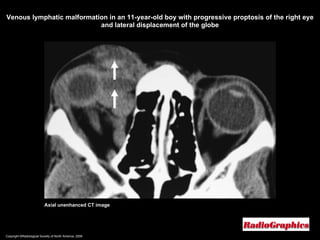

Lymphangioma (Venous Lymphatic malformations)   CT: Poorly circumscribed, heterogeneous masses of increased density. Bony remodeling may be present. Calcification is rare. Minimal to marked contrast enhancement may be present.  MR imaging: Relatively hypointense or hyperintense to brain on T1WI. Very hyperintense on T2WI. Fluid-fluid levels related to hemorrhages of various ages are characteristic of lymphangioma.

Copyright ©Radiological Society of North America, 2008 Axial unenhanced CT image Venous lymphatic malformation in an 11-year-old boy with progressive proptosis of the right eye and lateral displacement of the globe